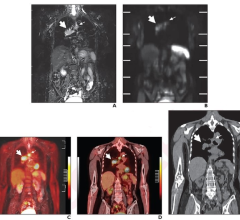

PET-MRI combines positron emission tomography (PET) and magnetic resonance imaging (MRI) into one imaging system. Positron emission tomography–magnetic resonance imaging (PET-MRI) is a hybrid imaging technology that incorporates magnetic resonance imaging soft tissue morphological imaging and positron emission tomography functional imaging.

July 31, 2024 — In a head-to-head comparison with FDG PET/CT, FDG PET/MRI demonstrated comparable or superior diagnostic ...